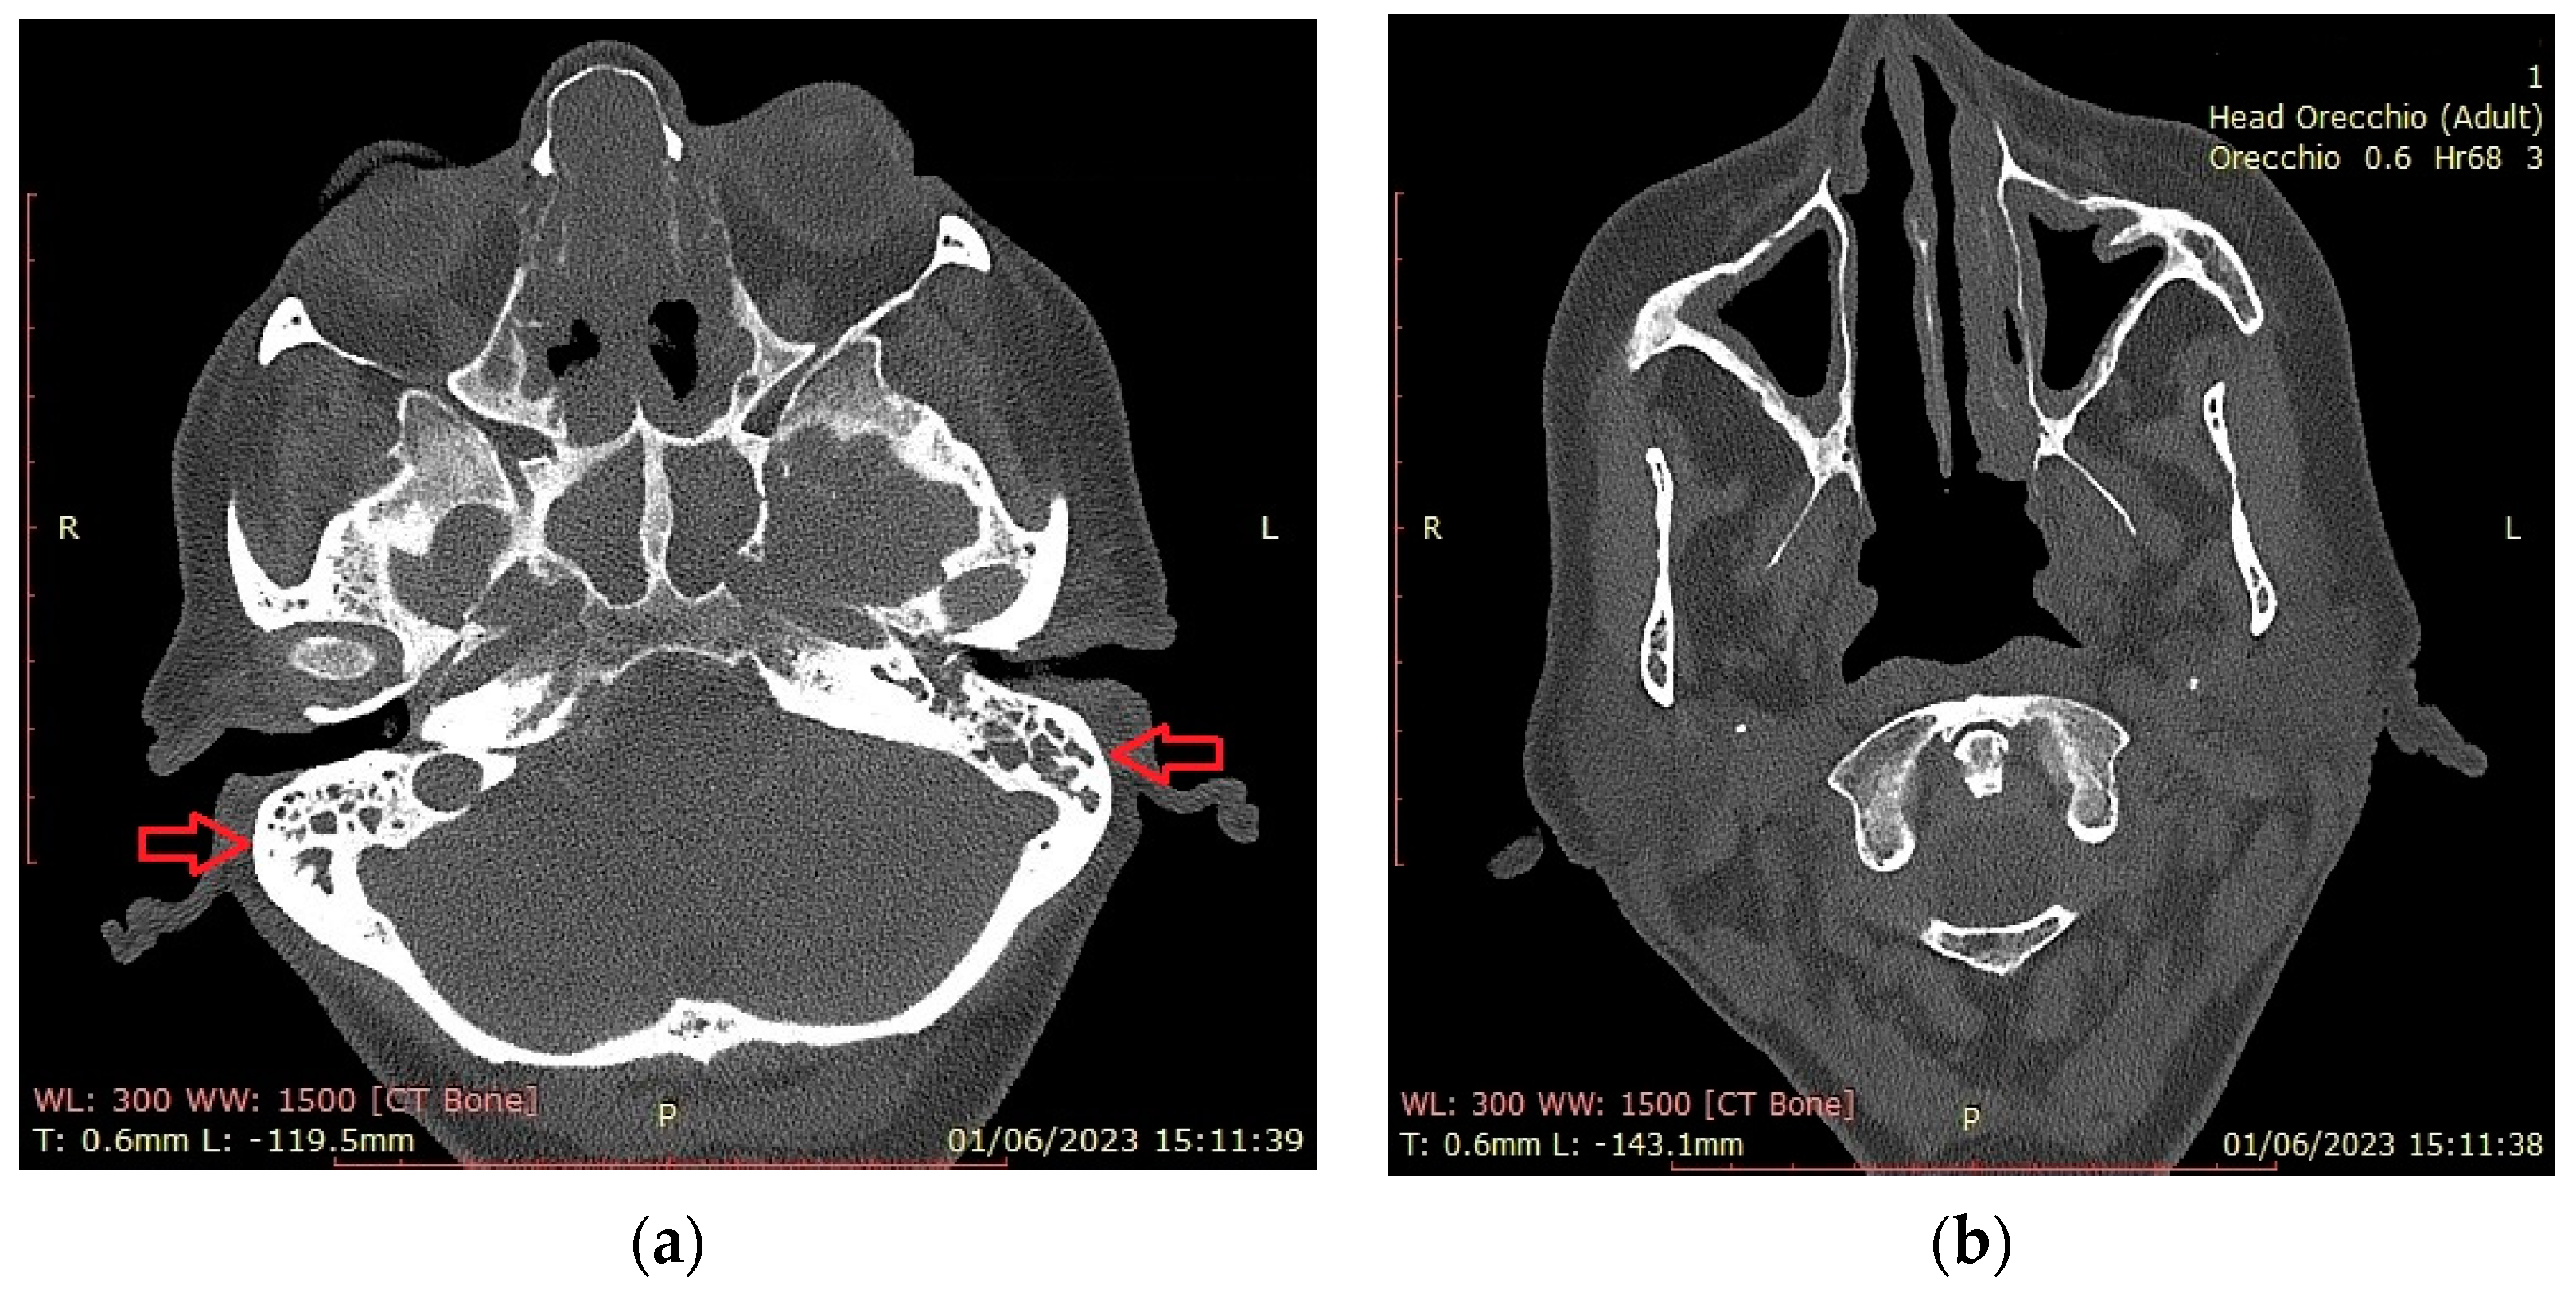

4.1. Nasal and Sinus Involvement

4.2. Ear Involvement

| Mucoceles | 1 (4%) |